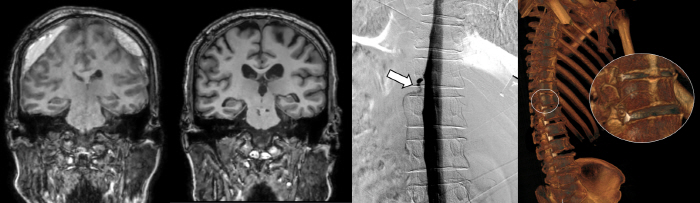

3D images of the fistula position (left) and cerebrospinal fluid venous fistula confirmed by positional CT spinal cord angiography.

Severance Hospital recently introduced DSM for the first time in Korea to overcome the limitations of such existing diagnostic methods. Digital Subtraction Myelography (DSM) can inject contrast agents into the spinal cord and check the flow of cerebrospinal fluid in real time with a monitor screen. Through this, it is possible to accurately find holes through which cerebrospinal fluid leaks.

Along with DSM, positional CT spinal cord angiography, which is being conducted by Severance Hospital, is all the latest techniques to diagnose cerebrospinal fluid venous fistula.

Patients who visited Severance Hospital this time were accurately diagnosed and treated with DSM tests and positional CT spinal cord angiography, restored cerebral pressure, and disappeared subdural hemorrhage. As a result, both cognitive decline and walking disorders seen by patients improved.